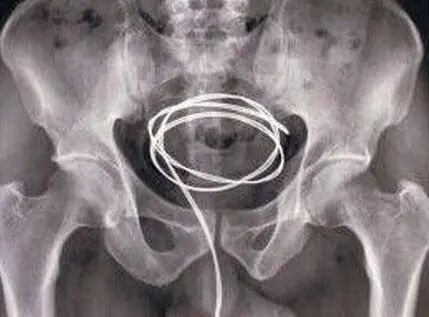

而像开头说的那种情况,可能存在某种性癖好,为了达到性快感而从尿道口塞入异物。

图片

如果异物卡在尿道可能引起急性尿潴留(尿不出尿来),如果在膀胱里面取不出来了,甚至可能需要开腹手术取出。